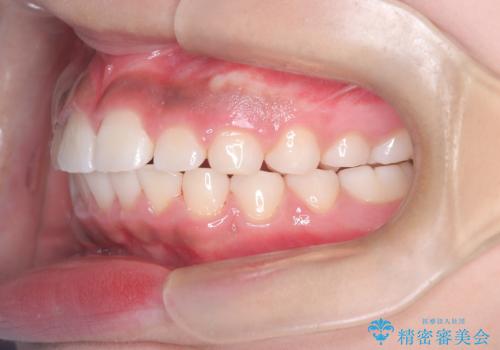

まず、上顎にリンガルアーチを装着し、歯列の幅を適正に維持しながら遠心移動をサポート。さらに、**TAD(矯正用アンカースクリュー)**を利用することで、奥歯を固定源とせずに前歯だけを後方へ移動させることが可能になりました。これにより、抜歯をせずに前歯の突出を抑え、バランスの取れた口元へと改善。治療後、患者様からは「抜歯せずに理想の仕上がりになり、大満足」とのお声をいただきました。